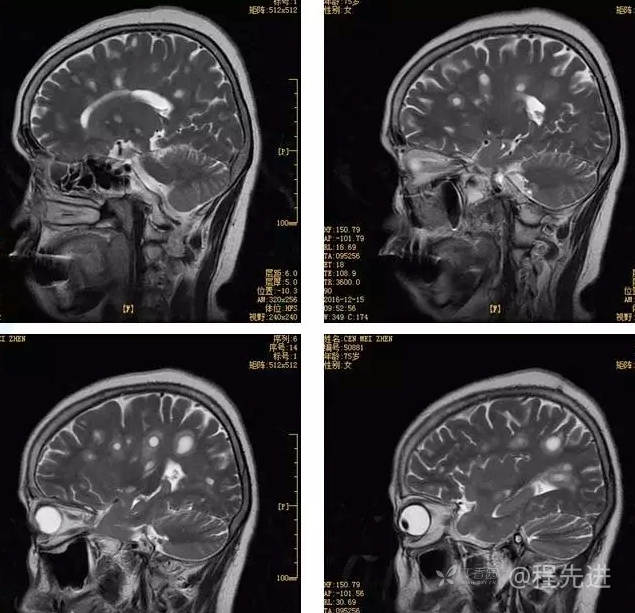

3月特别精彩病例|头晕伴左侧肢体乏力、行走不稳1周【结果已公布】

患者性别:女

患者年龄:75岁

简要病史:头晕伴左侧肢体乏力、行走不稳1周。否认高血压、脑梗塞、肝炎、糖尿病、肺结核病史。否认疫区疫水接触史。